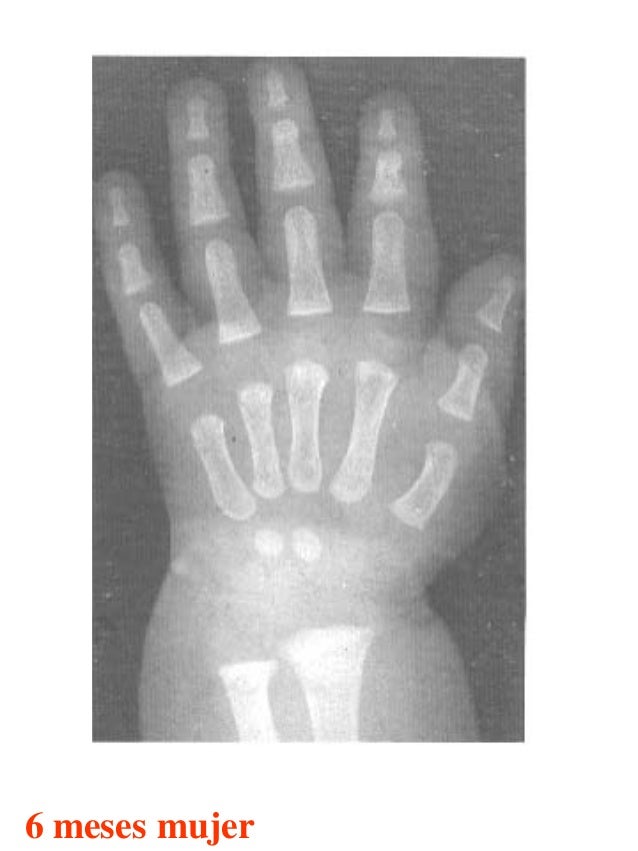

Figura 2 Imágenes de radiografías de mano y muñeca izquierda del

Figura 2 Imágenes de radiografías de mano y muñeca izquierda del Tablas De Greulich Y Pyle Edad Osea The greulich and pyle atlas is used to estimate the age of children and adolescents. El método de greulich y pyle(1) es un método simple de valoración de la edad ósea en pacientes pediátricos. El diagnóstico y la clasificación se basan en el examen físico, el análisis del crecimiento, la maduración ósea, la ecografía de útero y gónadas, y los. Tablas De Greulich Y Pyle Edad Osea.